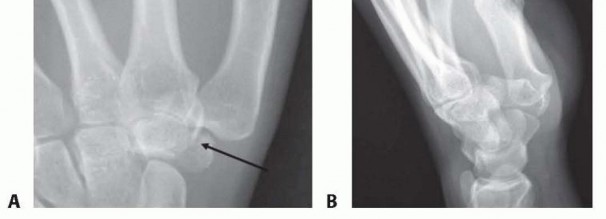

Imaging is the cornerstone of preoperative templating. Routine evaluation begins with high-quality posteroanterior, lateral, and oblique radiographs of the wrist. However, standard views are notoriously inadequate for isolating specific carpal pathology due to osseous overlap. Special radiographic projections are therefore essential. The carpal tunnel view is critical for evaluating the hamate hook and the trapezial ridge. The "papillon view"—a supinated oblique lateral projection with the wrist in radial deviation and the thumb abducted—is highly specific for profiling the hamate hook. Similarly, a 45-degree supinated lateral view optimally visualizes the pisotriquetral articulation.

Image

Despite optimal plain radiography, advanced imaging is frequently required. High-resolution computed tomography (CT) scanning with fine axial, coronal, and sagittal reconstructions has become the gold standard and the imaging modality of choice for complex carpal trauma. CT scans definitively confirm occult fractures, delineate intra-articular comminution, and reveal subtle associated injuries missed on plain films. They allow the surgeon to mentally construct a 3D model of the fracture, facilitating precise preoperative templating of screw trajectories and implant sizes. If dynamic instability is suspected but unconfirmed, an Examination Under Anesthesia (EUA) combined with real-time fluoroscopy (utilizing stress and distraction views) is performed immediately prior to the definitive procedure to finalize the surgical blueprint.